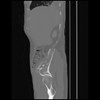

7 CUERPO,CE,Sagittal,3.000,CUERPO,Sagittal,